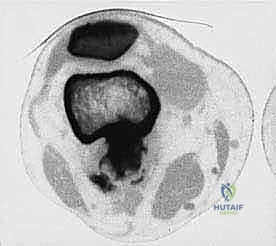

المرحلة الثانية: إعادة البناء العظمي (Skeletal Reconstruction)

بعد إزالة جزء من العظم (أو المفصل بأكمله)، يجب سد الفجوة. تتعدد الخيارات التقنية التي يوفرها الدكتور هطيف في صنعاء:

1. المفاصل الصناعية الكبيرة (Megaprostheses): مفاصل معدنية متطورة (من التيتانيوم) تُصمم خصيصاً لتعويض العظم المفقود، وتسمح للمريض بالحركة المبكرة.